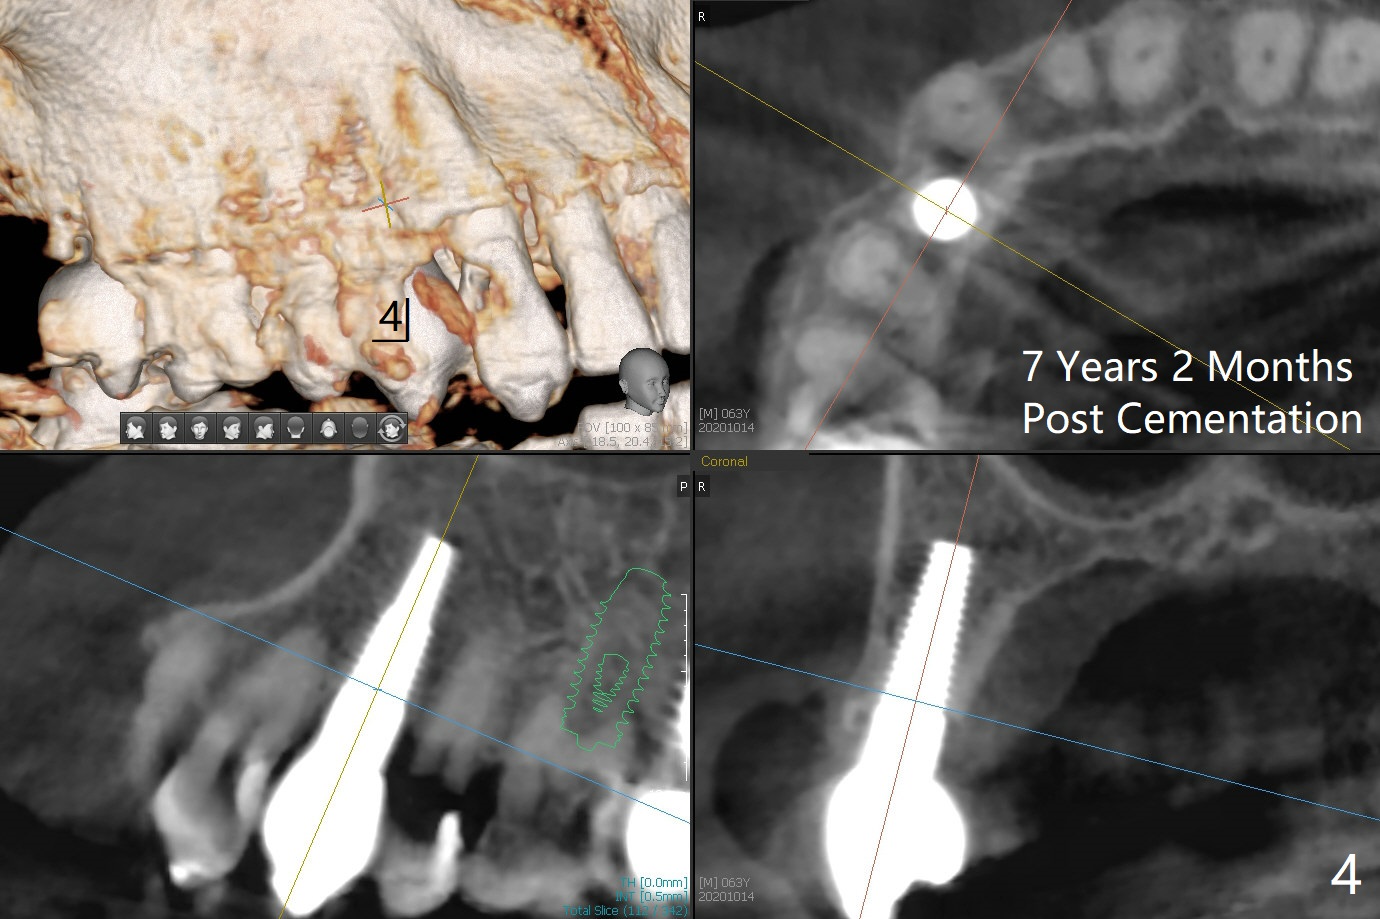

63岁女右上6远中龋齿在邻牙植牙牙冠粘固后2年8个月坏的严重(图一),病人决定拔除种植。之前嘱咐她回来修复,部分由于新冠病毒,她拖延治疗。今后需要建立一个植牙后完整随访和严密检查系统,减少继发龋。分析四个植牙(图二,四至六)表明骨质宽度优越,右上6即刻种植应该没问题(图三)。植体选择与邻近一致。Prevent Molar Periimplantitis (Protocols, Table) No Neighboring Caries Metronidazole Magicore Cases 手术 2 Xin Wei, DDS, PhD, MS 1st edition 10/14/2020, last revision 11/17/2020